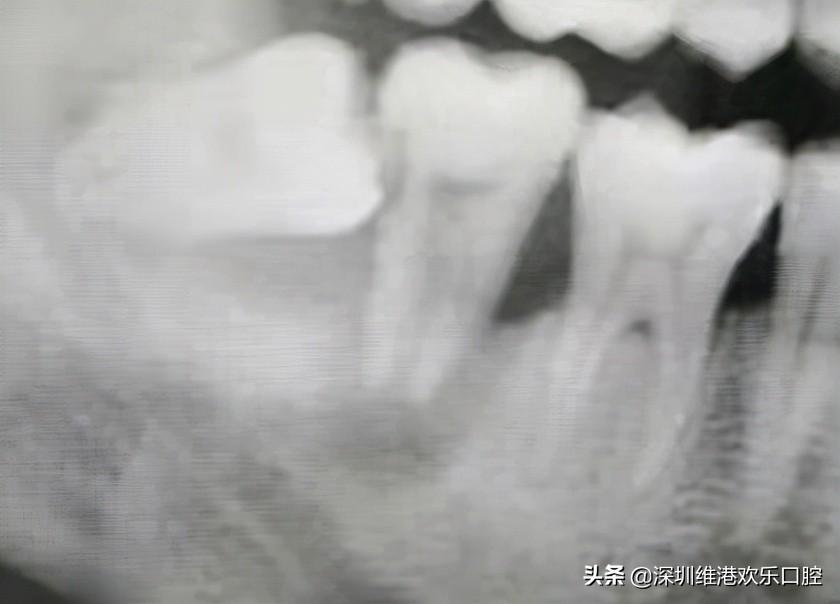

一位患者,智齒長(zhǎng)歪頂壞了鄰牙,導(dǎo)致鄰牙鬆動(dòng),極其容易脫落,患者自己也一度以為可能保不住了。但是高主任在仔細(xì)檢查了患者的實(shí)際情況,認(rèn)為還有保留住的可能。所以高利民主任先把這個(gè)極松的7號(hào)牙和6號(hào)牙用玻璃離子粘結(jié)穩(wěn),先將7牙磨低磨小開(kāi)髓置Fc棉暫封,然后拔掉智齒,等7牙慢慢恢復(fù)。經(jīng)過(guò)幾個(gè)月后,患者的原始牙得到了很好的恢復(fù)保留。